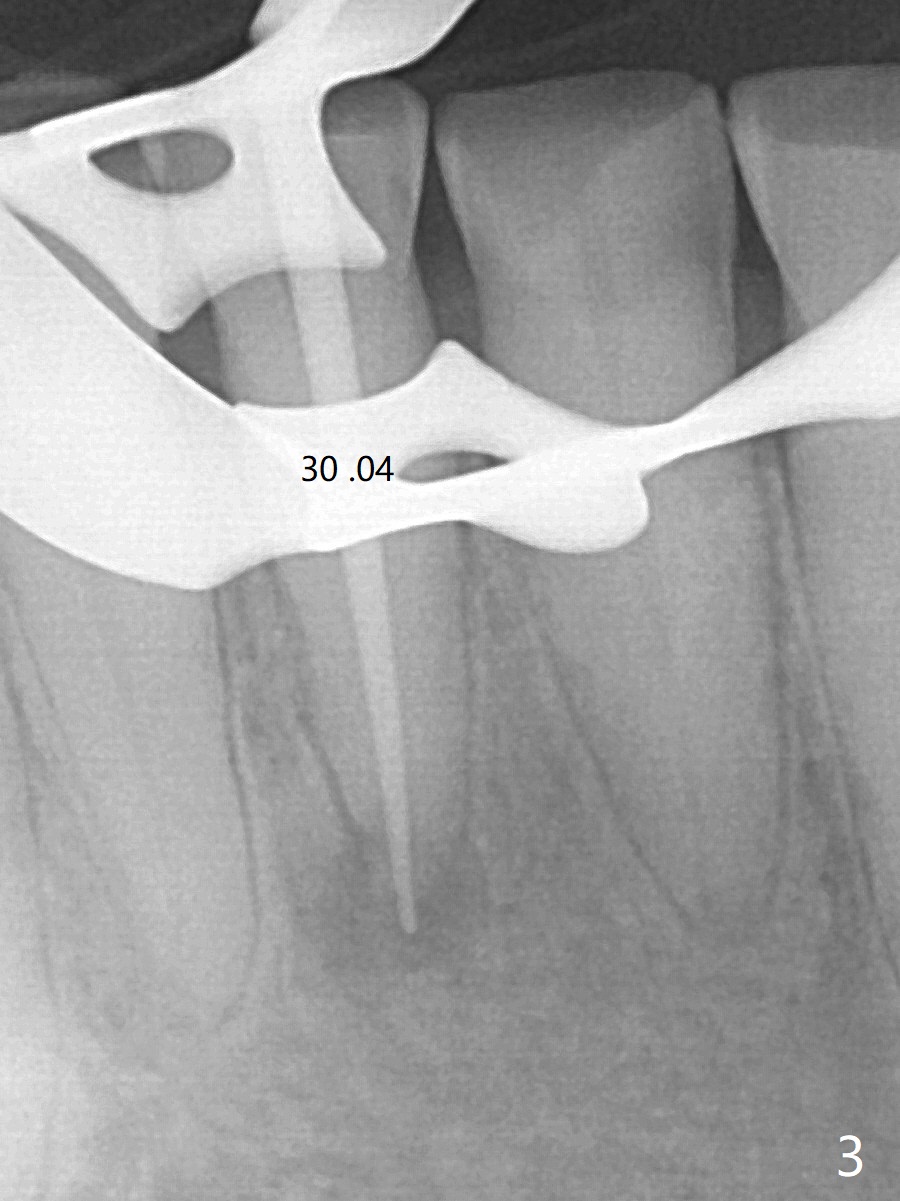

A 64-year-old man has multiple restoration and loves to eat crab. The lower incisors have severe wear. The tooth #25 is discolored with pulpal exposure and periapical radiolucency (Fig.1, 2 *). After insertion of 30/.04 master cone (Fig.3 (1 year 3 months post diagnosis)), RCT is finished with BioRoot RCS (bioceramic) and single GP (Fig.4). Nearly 10 months later, the patient returns with sinus track associated with the tooth #24 with PARL (Fig.5 *).